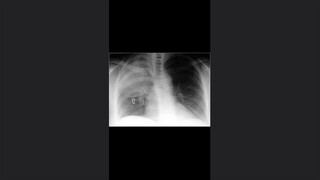

TORAX MEDIASTINO PULMON- CORAZON

Signos de importancia del tórax

Generalidades del tórax y pulmón